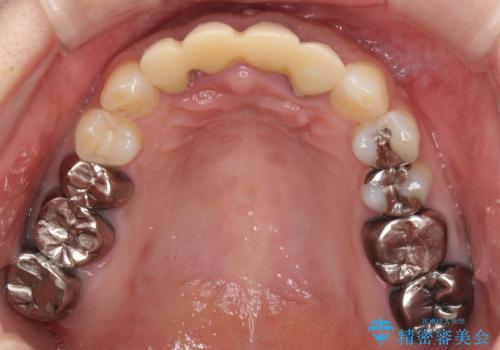

- 地元の歯科医院にて前歯4歯を仮歯に替えたものの、汚れていることが気になるとのことで来院された患者様です。

不適な仮歯の影響で歯肉が腫れていたため、新しい仮歯に替えた後に歯肉の腫れが引くのを待ち、オールセラミッククラウンにて補綴することとしました。

根尖病変が原因で、膿が出てきている歯があったため、仮歯を置き換える際に根管治療を行うこととしました。

仮歯を変えたことで歯肉の腫れは引き、根管治療も功を奏して膿の出口はきれいに消退しました。